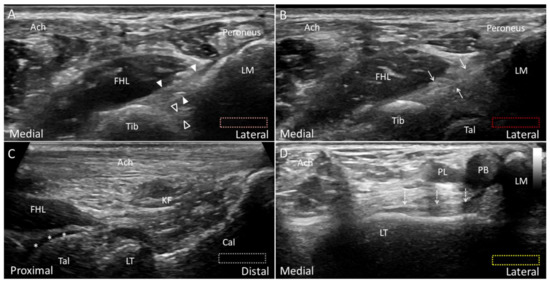

4.4. Plantaris Tendon

4.4.1. Anatomy

4.4.2. Scanning Technique

4.4.3. Clinical Relevance